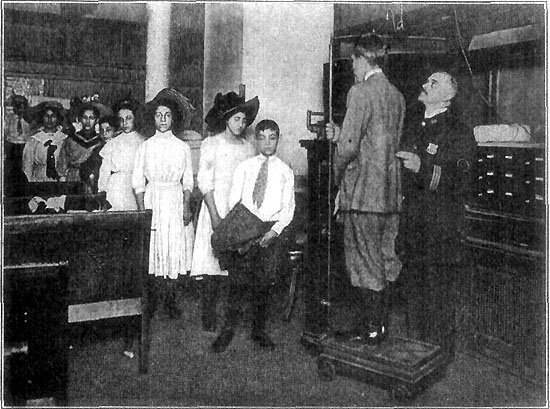

105 A Board of Health Examination for Working Papers

106 A Test of Clear Head and Steady Nerves